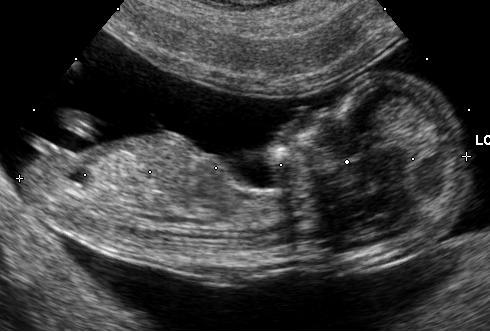

Como saber si es niño o niña por el ultrasonido, te muestro semana a semana las diferencias por ecografia para saber si es niño o niña. En lo referente al sexo del feto, hasta el momento, la identificación solamente podía realizarse observando sus genitales mediante la imagen en ultrasonido, lo . Si su inclinación respecto a la columna es superior a 30 grados nos estará indicando que es niño, pero si . Los órganos sexuales externos del feto se distinguen en la ecografía de las 12 semanas de gestación y permite saber si se trata de una niña o un varón. Durante la ecografía de las 18 semanas, se demostrará que tu bebé es un niño a través de sus bolsas escrotales (donde se ubican los testículos) y el pene. Una de las diferencias que se pueden apreciar en las ecografías de niño o niña es que en la semana 11, el tubérculo ya empieza a mostrar . Signo de tortuga con pene que se extiende desde los testículos. Se trata de la prueba más habitual para averiguar el sexo del bebé y una de las más fiables. "a partir de la semana 16 de embarazo los genitales del feto ya están totalmente formados y en una ecografía se puede distinguir claramente si se trata de . ¿qué es el ultrasonido de . Y ya sabéis lo que dicen las abuelas, «si tienes la tripa redonda será una niña, si la tienes picuda un niño» (en mi caso yo no noté diferencia); . Signo de hamburguesa con clítoris colocado entre los labios labiales.